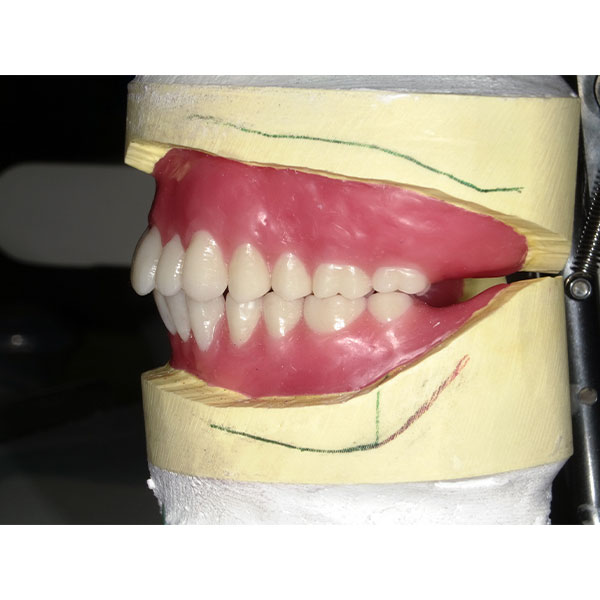

Après la mise en moufle et l'ébouillantage, les dents ont été repositionnées, conditionnées et des caractérisations blanchâtres, pourpres, orange clair, bleues et roses ont d'abord été réalisées au niveau du le bouclier labial. La base a ensuite été incrustée de résines pour prothèses de couleurs orange-rouge, rouge foncé, rouge clair, rose et rose foncé, et tous les polymères à chaud ont été pressés en une seule fois. Après le stockage sous pression, les prothèses finies ont été démouflées, finies et polies. La stratification anatomique tridimensionnelle de VITAPAN EXCELL en masse d'émail, de collet et de dentine avait un aspect absolument naturel dans l'anatomie muco-gingivale reproduite de la base prothétique. Le patient a pu s'habituer rapidement à sa nouvelle prothèse, notamment grâce à l'effet esthétique réussi. Après une courte phase d'adaptation et des corrections minimes dans l'environnement biodynamique, il s'est très bien débrouillé avec sa première restauration prothétique amovible complète et en était pleinement satisfait.